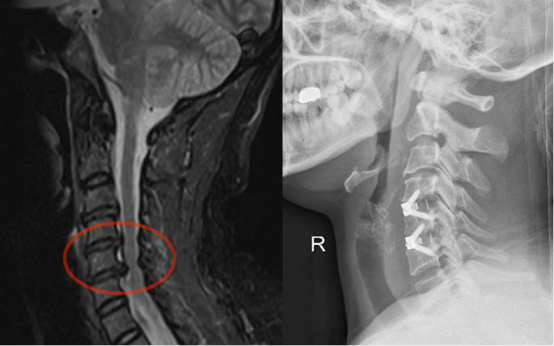

2.下颈椎

⑴颈椎前路手术:椎间盘切除Cage椎间融合术;椎体次全切椎管减压钛笼钛板内固定术。⑵颈椎后路手术:后路单开门、双开门椎管扩大成形术;侧块螺钉钉棒内固定术。⑶颈椎前后路联合手术,一期完成治疗复杂性颈椎病。

图注:手术前MRI显示多节段颈椎间盘突出、椎管狭窄、脊髓受压,手术予微创切除颈4/5、颈5/6椎间盘并于椎间植入Cage行椎体间融合。